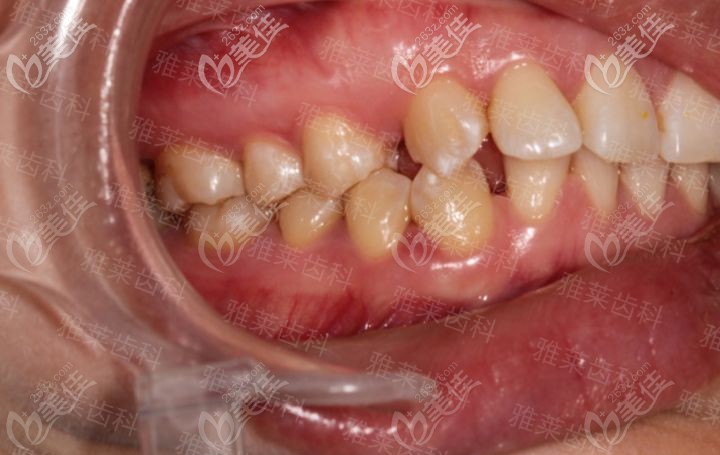

杭州雅萊齒科紀亞梅是杭州有名的牙齒矯正醫(yī)生,找她看牙靠譜嗎? b1231 G0 V0

杭州雅萊齒科紀亞梅是杭州有名的正畸醫(yī)生,很多人關(guān)注她,如果找他做隱形矯正不知道靠譜嗎?有沒有案例可參考。